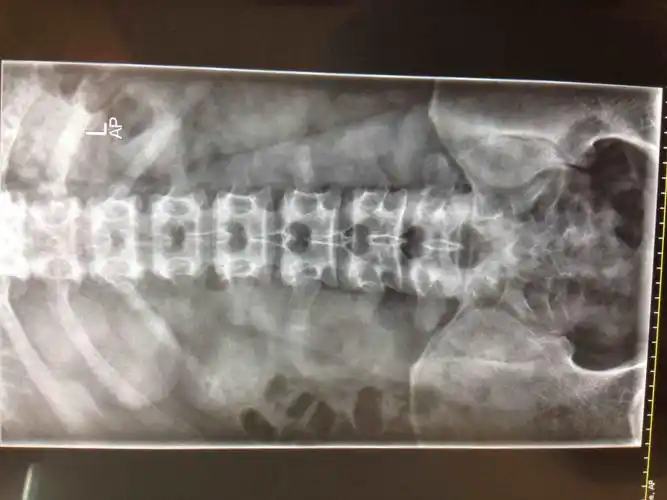

【病例】腰大肌血肿1例ct影像表现

临床表现较为隐匿,或仅在相应部位发现肿块;ct表现腰大肌局部不规则